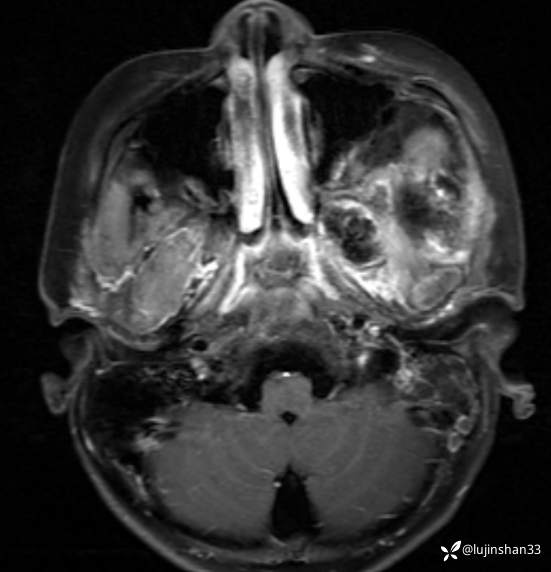

简要病史:患儿父母半年前发现患儿左颞部较右侧突起,无伴随症状,未重视未诊治,1月前,患儿左颞部肿物长大,伴头晕,向一侧倾倒感,头痛,两次剧痛,余为胀痛,偶有夜间出现左下颌区域皮肤麻木,咀嚼时左面部疼痛,10天前,患儿出现左眼睑肿胀伴疼痛,睁眼疼痛加重,不伴视力障碍,无畏寒发热,无意识障碍,无饮水呛咳,在XX同仁医院行颅脑核磁示:左侧颞下窝占位。门诊以“颞下窝占位(左)”收入院。患者目前精神状态良好,体力正常,食欲正常,睡眠正常,体重无明显变化,大便正常,排尿正常。

体格检查:左侧颞部可见约7*4cm大小肿物突起,质软,边界不清,局部皮肤无红肿,伴疼痛,左眼睑肿胀,不能睁眼,角膜反射检查不能配合。嗅觉粗测正常,双眼视力粗测正常,双侧瞳孔等大同圆,直径约3mm,对光反射灵敏。眼底检查未见异常。右眼睑无下垂,左眼睑肿胀,眼裂约4mm,无眼球下陷,眼球各方向活动自如。双面部痛温觉正常。双侧颞肌、咀嚼肌无萎缩,咀嚼动作基本对称,张口无歪斜,伸舌无偏斜。双侧额纹对称,闭眼无露白,双侧鼻唇沟无变浅,鼓腮无漏气、示齿时口角无明显偏斜。双侧咽腭弓对称,悬雍垂居中,双侧咽反射正常。声音无嘶哑,无饮水呛咳,无吞咽困难。双侧斜方肌、胸锁乳突肌均无萎缩,双侧转头、耸肩对称有力。

颞骨CT:2020年12月

临床诊断:颅中窝、颞下窝小圆细胞恶性肿瘤

治疗经过:颅中窝入路侧颅底、颞下窝肿瘤切除、腹部脂肪取出、术腔填塞术